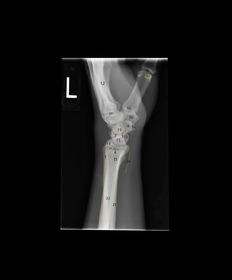

| PA Wrist | wrist externally rotated - joint spaces closed, proximal metacarpals superimposed, carpals superimposed radiocarpal joint is closed |

| Oblique Wrist | over rotation radial styloid is not seen in profile |

| Lateral Wrist | under rotation - radius and ulna are not superimposed, hand is internally rotated |

| PA Wrist | ANATOMY: all carpals including midmetacarpals and distal radius/ulna CRITERIA: true PA is marked by symmetry of proximal metacarpals carpals should be free of superimposition of the metacarpals and radius/ulna POSITIONING: CR perpendicular @ midcarpals |

| Oblique Wrist | ANATOMY: carpals on lateral side of wrist, scaphoid CRITERIA: scaphoid well demonstrated 45 degree obliquity POSITIONING: CR perpendicular @ midcarpals |

| L | CRITERIA: radius/ulna should be superimposed thumb should be forward metacarpals superimposed POSITIONING: CR perpendicular @ midcarpals |